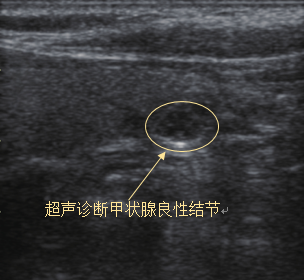

甲状腺细针穿刺活检通过穿刺针吸取细胞成分,术前进行病理诊断,该检查具有微创、操作简便、对结节多点取材、重复穿刺,并发症少等优点。

甲状腺细针穿刺活检由FNAB-CAT指南、NCCN指南、ATA指南、 ESMO指南A级推荐,有高敏感度和高特异度,被国内外医疗工作者广泛认可,其敏感度和特异性呈逐年递增且均已高于90%

FNA活检针的选择:22G-23G,长度5-10CM。